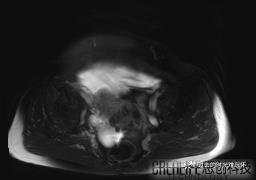

患者性别:女

患者年龄:65岁

主诉: 发现腹部隆起半年余。无其他明显不适。

浆液性囊腺瘤 (22)